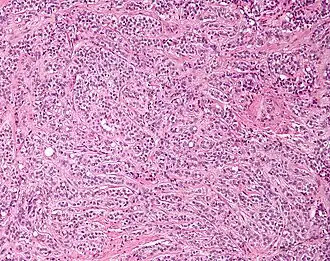

| Micrograph of a Sertoli cell tumour. H&E stain. | |

A Sertoli cell tumour, also Sertoli cell tumor (US spelling), is a sex cord–gonadal stromal tumour of Sertoli cells. They can occur in the testis or ovary. They are very rare and generally peak between the ages of 35 and 50. They are typically well-differentiated and may be misdiagnosed as seminomas as they often appear very similar.[1]

Microscopy and immunohistochemistry are the only way to give a definitive diagnosis, especially when there is a suspected seminoma.[3]